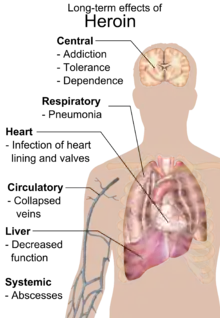

Complicaciones

Uno de los factores principales que llevan a una variedad de complicaciones graves, es el efecto narcótico de la heroína. Las complicaciones surgen cuando se toma la heroína como una droga que puede dividirse en varias tomas diarias causando alteraciones fisiológicas por la acción del diacetilmorfina en el cuerpo humano y debido a las impurezas del producto. Para los individuos con adicción a esta droga la más común y peligrosa complicación es una sobredosis. Según varios informes, el 50-60% de los consumidores de opiáceos al menos una vez sufrieron una sobredosis. También se puede desarrollar psicosis y estados epilépticos.[58] Además, al tomar la heroína, hay consecuencias a largo plazo que se manifiestan en una variedad de trastornos de la microcirculación, enfermedad en el hígado, y en los componentes que actúan durante la depresión del sistema nervioso central.[59] Además de los efectos tóxicos directos de heroína en el cuerpo, su consumo puede afectar seriamente la salud debido a una variedad de impurezas contenidas en el producto, debido a la falta de agentes de limpieza o productos intencionalmente añadidos de reventa para obtener mayores beneficios mediante mezclas con una disminución de su cantidad de narcóticos para así obtener más beneficios en la venta. También el mismo diacetilmorfina y las impurezas contenidas en la administración de la droga pueden desarrollar una reacción alérgica marcada por angioedema y anafilaxia, aunque estos efectos secundarios no ocurren con demasiada frecuencia, pero podría representar un grave peligro para la vida del usuario en el caso de producirse.

Cuando las inyecciones intravenosas son a menudo desarrolladas se genera flebitis, y la endocarditis con afectación de la válvula tricúspide del corazón. Si se usa jeringas o contenedores para solución o para la administración intravenosa, se corre el riesgo de desarrollar diversas infecciones (ETS) como el VIH o la hepatitis.